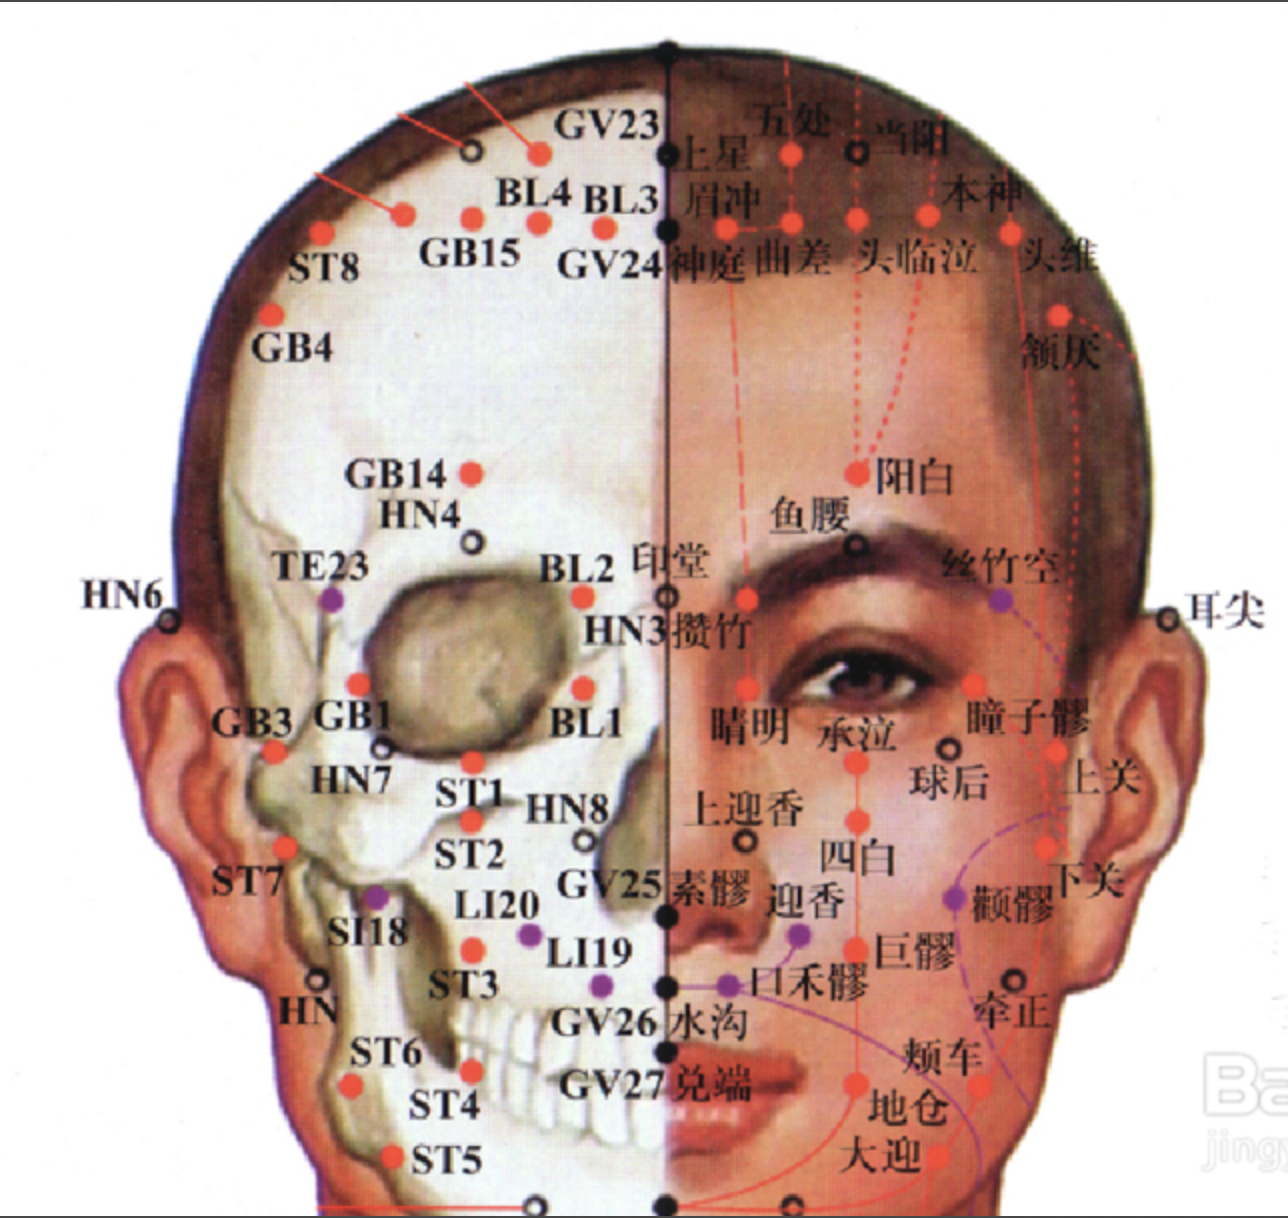

【(三)足阳明胃经(图10-21-1)】

图 10-21-1 足阳明胃经循行及常用腧穴

1、时辰 辰时 7 ~ 9

2、歌诀 四十五穴足阳明,承泣四白巨髎(liáo)经,地仓大迎下颊车,下关头维对人迎,水突气舍连缺盆,气户库房屋翳寻,膺窗乳中下乳根,不容承满出梁门,关门太乙滑肉起,天枢外陵大巨里,水道归来达气冲,髀关伏兔走阴市,梁丘犊鼻足三里,上巨虚连条口底,下巨虚下有丰隆,解溪冲阳陷谷同,内庭厉兑阳明穴,大趾次趾之端终。

3、经脉循行 起于鼻翼两侧(迎香),上行到鼻根部与足太阳经交会,向下沿鼻外侧进入上齿龈内,回出环绕口唇,向下交会于颏(kē)唇沟承浆处,再向后沿口腮后下方,出于下颌(hé)大迎处沿下颌角颊车,上行耳前,经上关,沿发际,到达前额(前庭)。

面部支脉:从大迎前下走人迎,沿着喉咙,进入缺盆部,向下过膈,属于胃,联络脾脏。

缺盆部直行的脉:经乳头,向下夹脐旁,进入少腹两侧气冲;

胃下口部支脉:沿着腹里向下到气冲会合,再由此下行至髀(bì)关,直抵伏兔部,下至膝盖,沿胫骨外侧前缘,下经足跗;进入第二足趾外侧端(厉兑)。

胫部支脉:从膝下 3 寸(足三里)处分出进入足中趾外侧端。

足跗部支脉:从跗上分出,进入足大趾内侧端(隐白)与足太阴脾经相接。

4、主要病候 肠鸣腹胀、水肿、胃痛、呕吐或消谷善饥、口渴、咽喉肿痛、鼻衄、胸部及膝髌(bìn)等本经循行部位疼痛、热病、发狂等。

5、主治概要 主治胃肠病、头面、目鼻、口齿痛、神志病及经脉循行部位的其他病证。

承泣

【定位】 在面部,瞳孔直下,当眼球与眶下缘之间。

【主治】 目赤肿痛,流泪,夜盲,眼睑瞤(rún)动,口眼歪斜。

【配伍】 配太阳治目赤肿痛,配阳白治口眼歪斜。

【刺灸法】 以左手拇指向上轻推眼球,紧靠眶缘缓慢直刺 0.5 ~ 1.5 寸,不宜提插,以防刺破血管引起血肿。

【附注】 足阳明经、阳跷、任脉交会处。

四白

【定位】 在面部,瞳孔直下,当眶下孔凹陷处。

【主治】 目赤痛痒,目翳,眼睑瞤(rún)动,口眼歪斜,头痛眩晕。

【配伍】 配阳白、地仓、颊车、合谷治口眼歪斜,配攒竹治眼睑瞤(rún)动。

【刺灸法】 直刺或斜刺 0.3 ~ 0.5 寸,不可深刺。

地仓

【定位】 在面部,口角旁约 0.4 寸,上直对瞳孔(图 10-21-2)。

【主治】 口歪,流涎,口角瞤(rún)动。

【配伍】 配颊车、合谷治口歪、流涎。

【刺灸法】 向颊车方向平刺 0.5 ~ 0.8 寸。

【附注】 手足阳明经、阳跷脉交会穴。

颊车

【定位】 在面颊部,下颌角前上方约 1 横指(中指),当咀嚼时咬肌隆起最高点,按之凹陷处。

【主治】 口歪,齿痛,颊肿,口噤不语。

【配伍】 配地仓治口眼歪斜。

【刺灸法】 直刺 0.3 ~ 0.5 寸,平刺 0.5 ~ 1 寸。

下关

【定位】 在面部耳前方,当颧弓与下颌切迹所形成的凹陷中(图 10-21-3)。

【主治】 耳聋,耳鸣,聤(tíng)耳,齿痛,口噤,口眼歪斜。

【配伍】 配翳风治耳疾。

【刺灸法】 直刺 0.5 ~ 1 寸。

【附注】 足阳明、足少阳经交会穴。